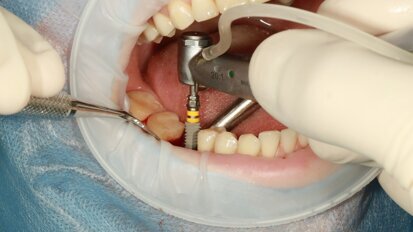

Review study compares machined and sandblasted dental implant surfaces

BUDAPEST, Hungary: Studies have shown that the implant surface roughness influences the degree of biological integration and success rates of dental ...